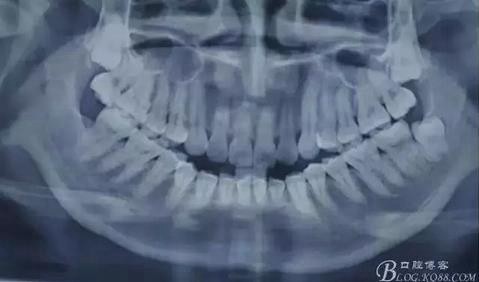

患者、李xx、女、21歲。主訴:因正畸需要拔出上頜埋伏智齒。??茩z查:18、28均未萌出,捫及上頜結(jié)節(jié)后份,未有明顯隆起。全景片檢查:18、28高位近中埋伏阻生,牙冠近鄰17、17根部。診斷:高位近中埋伏阻生。術(shù)前與患者溝通,有上頜竇穿通風(fēng)險?;颊吆炐g(shù)前知情同意書。

圖1.術(shù)前全景片影像檢查:18、28高位近中阻生,牙冠均緊鄰17、27牙頸部,牙根近鄰上頜竇。